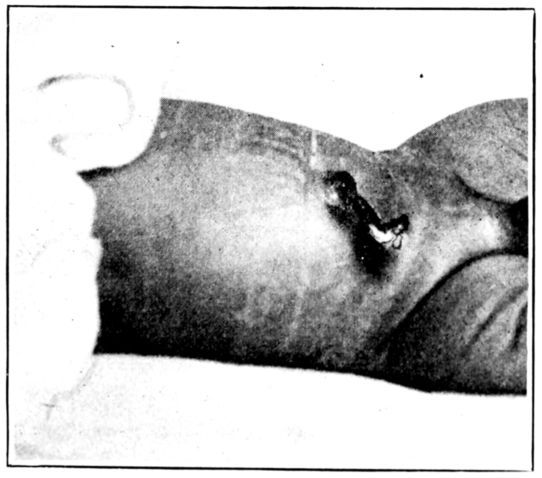

| 149. | Umbilical cord immediately after birth | 457 |

| 150. | The same four days later | 457 |